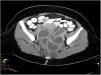

A 48-year old woman presented with fever, emesis and right upper quadrant abdominal pain. She denied other symptoms and sexual activity. Physical examination revealed RUQ abdominal tenderness. Laboratory tests showed 17000/mm3 white blood cell count (range 4000–10000/mm3), 6, 22ng/mL procalcitonine (normal <0.5ng/mL) and 1.64mg/dL bilirrubin (range 0–1.2mg/dL). Serum liver enzymes were also increased: GOT 89U/L (range 4–40U/L), GGT 89U/L (range 5–41U/L) and GGT 178U/L (range 10–71U/L). She had been cholecystectomized a few years ago, and therefore a cholangitis was suspected. Abdominal ultrasound demonstrated no hepatobiliary or intestinal abnormalities. Despite antibiotic treatment for 72h with ciprofloxacine and metronidazole, the patient kept febril and started with lower abdominal pain. She denied vaginal discharge and urinary tests were normal. New laboratory test revealed worsening of C-reactive-protein (17mg/dL, normal <0.5mg/dL) and liver enzymes which persisted despite changing treatment to piperaciline-tazobactam. The combination of a painful liver without evidence of hepatitis or biliary obstruction by abdominal ultrasound and lower abdominal pain raised the suspicion of Fitz-Hugh-Curtis syndrome. A computed tomography (CT) scan was finally performed 7 days after admission which showed hepatomegaly, piosalpinx and tubo-ovarial abscesses, all consistent with pelvic inflammatory disease (Fig. 1). The patient underwent laparoscopic surgery to remove tubo-ovarial abscesses, completed 3 weeks of piperaciline-tazobactam and was finally discharged.

Increased enhancement along the hepatic surface on CT during arterial phase together with pelvic inflammatory disease findings may suggest the diagnosis. Recent studies demonstrated that dynamic abdominal CT scan can significantly improve depiction of perihepatic enhancement. This may reflect increased blood flow at the inflamed hepatic capsule, which is consistent with the laparoscopic findings of inflammation and exudate formations. Perihepatic capsular enhancement in the early phase may completely disappear after treatment.5